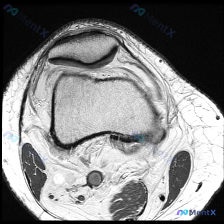

今天看到一个很有代表性的读片问题,整理一下思路分享给大家。 病例/问题背景 问题:针对一张标注怀疑「软骨异常」的膝盖MRI T1加权轴位图像,描述可见的视觉表现。 --- 影像基础信息 图像为单张膝关节水平面T1加权成像(T1WI),这个序列的基本信号特点是:骨髓、皮下脂肪呈高信号(亮),肌肉呈中等...